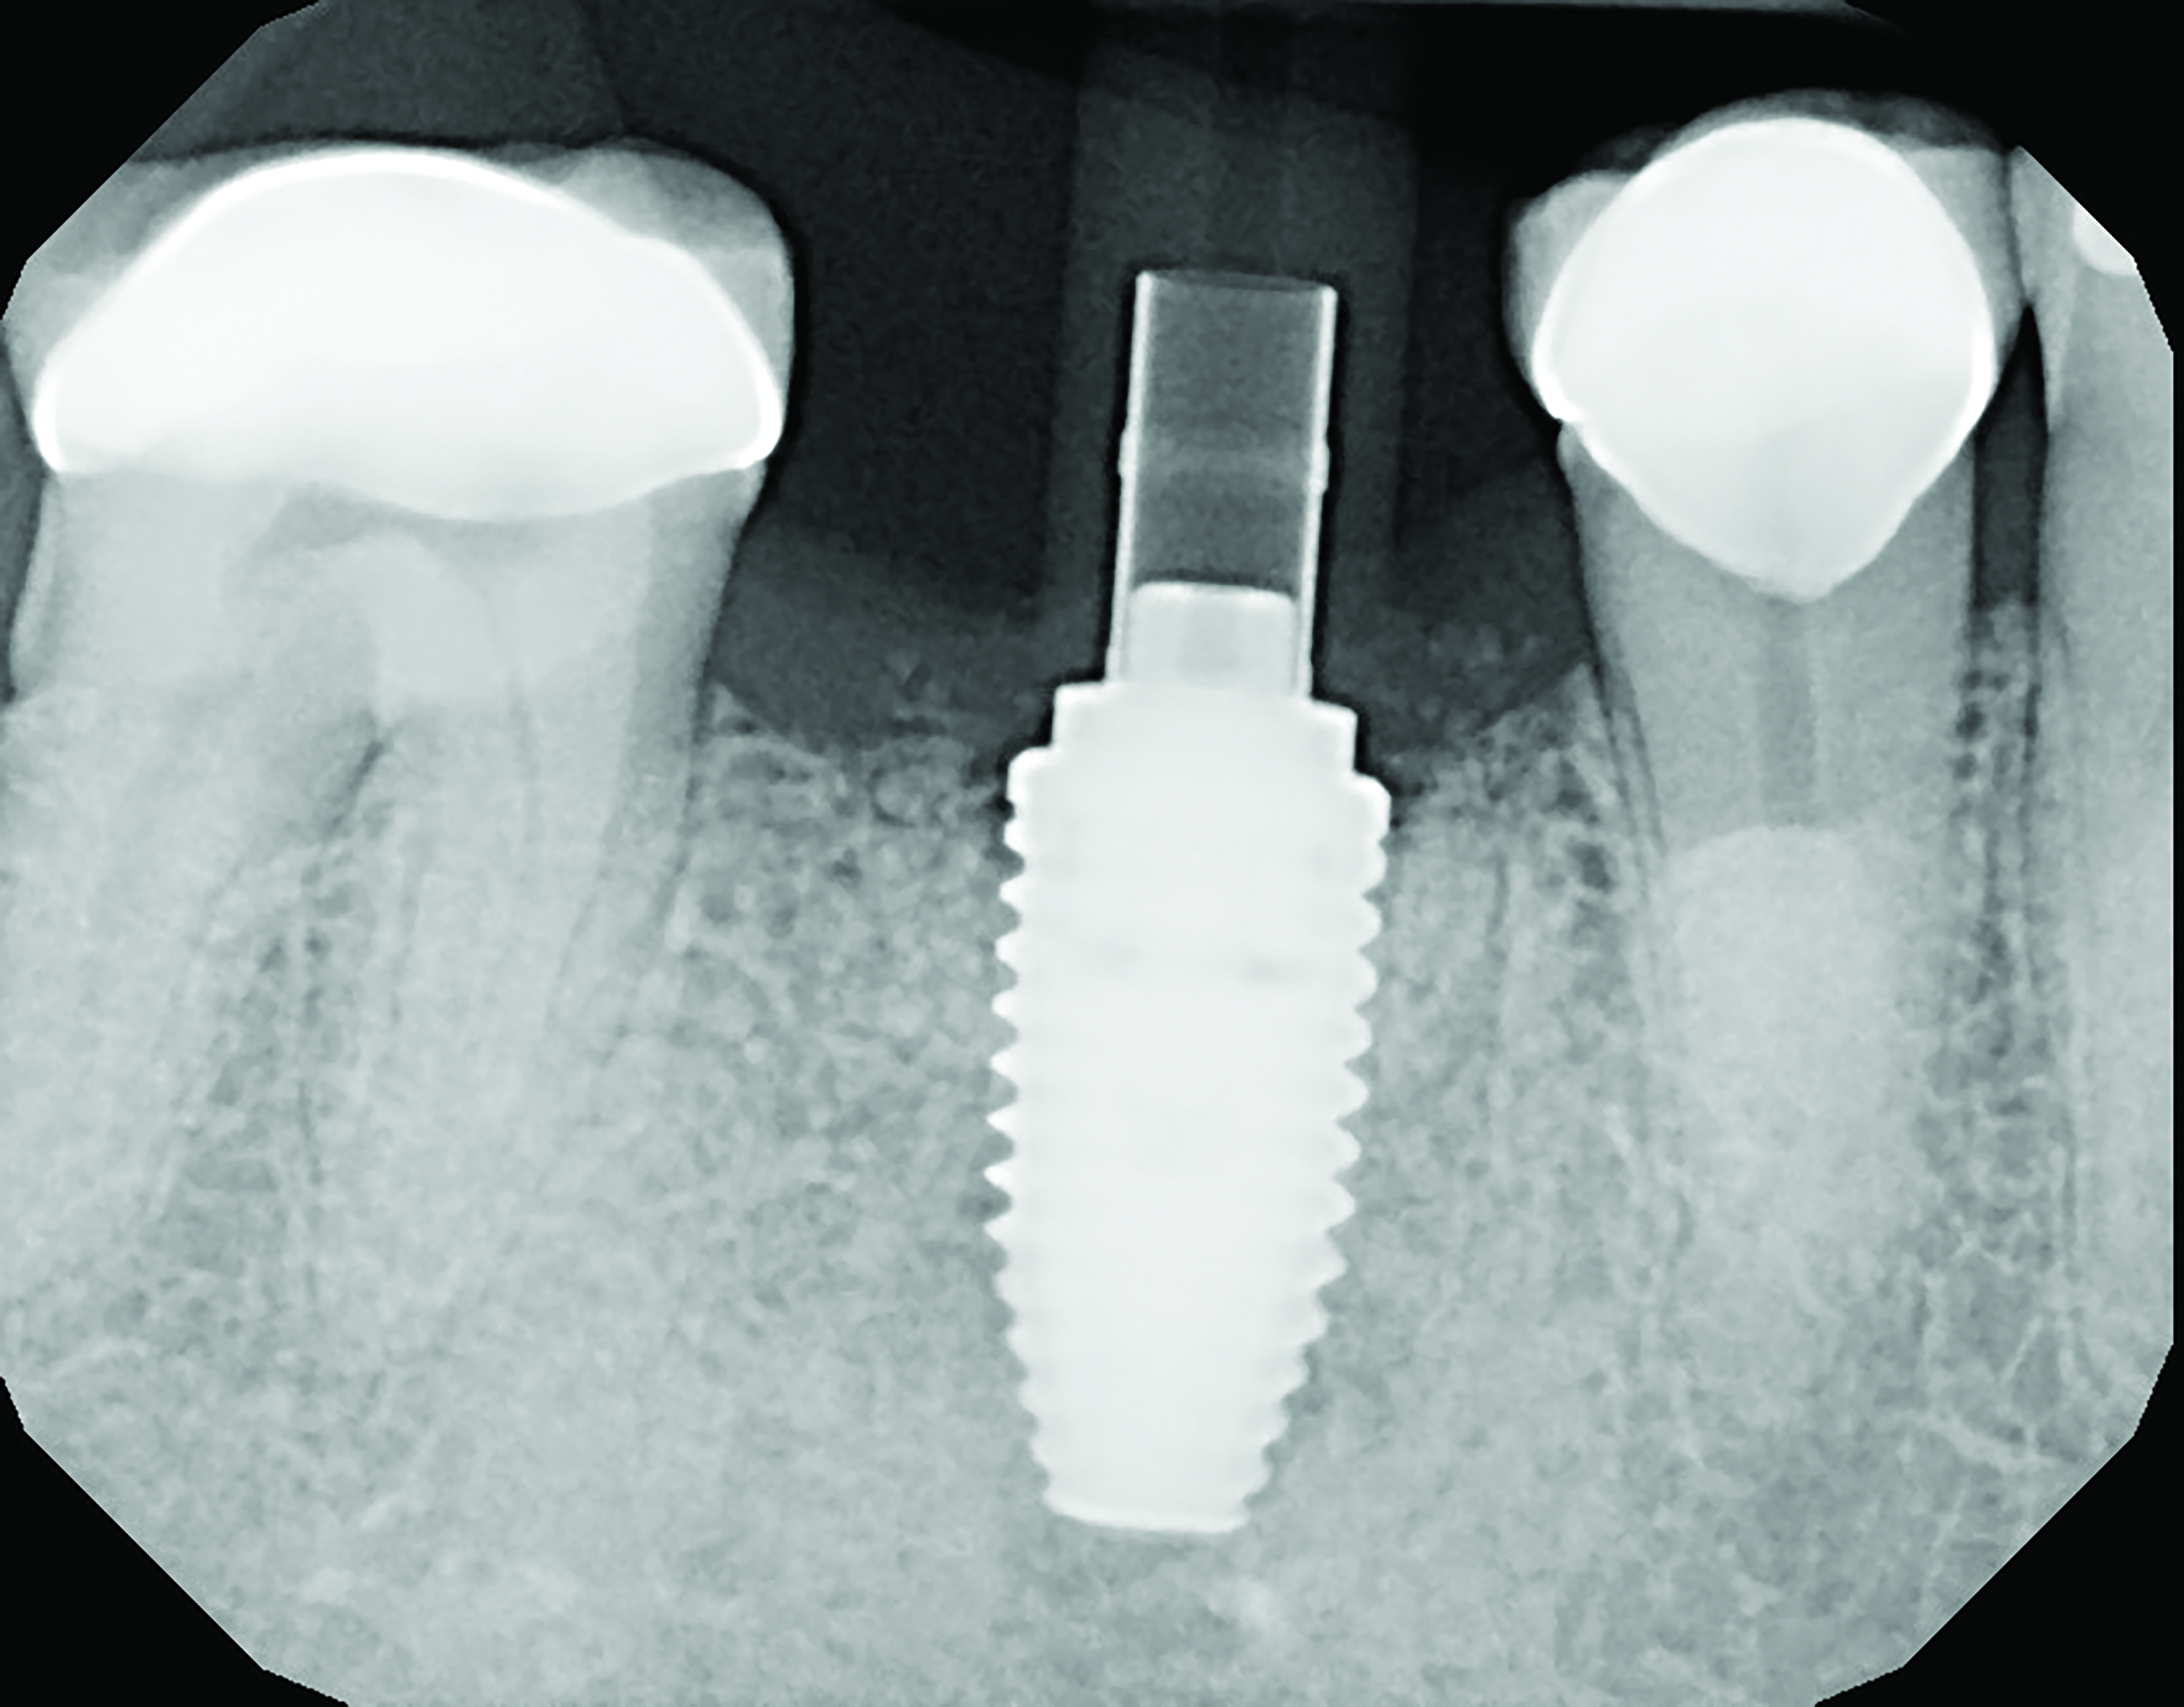

Case Presentation

A mandibular right first molar was extracted due to an advanced Class III furcation and an irreversible pulpitis—a combination lesion. An immediate implant placement protocol was elected, and a PEEK abutment was placed on the implant (Figure 1). After 3 months of healing, a scan body was placed on the osseointegrated implant (Figure 2 and Figure 3), and an intraoral scan was taken (TRIOS Pod) (Figure 4) for the fabrication of a screw-retained crown.

Fig 1. Immediate implant placement with a PEEK healing abutment to contour soft tissue, mandibular right first molar.

Figure 1